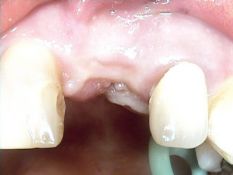

Patiente ayant fracturé sa dent suite à un choc. L’implant est mis en place après

une courte période de cicatrisation de la zone traumatisée. Une couronne provisoire en résine

est placée le jour de l’intervention (vue clinique après 6 semaines).